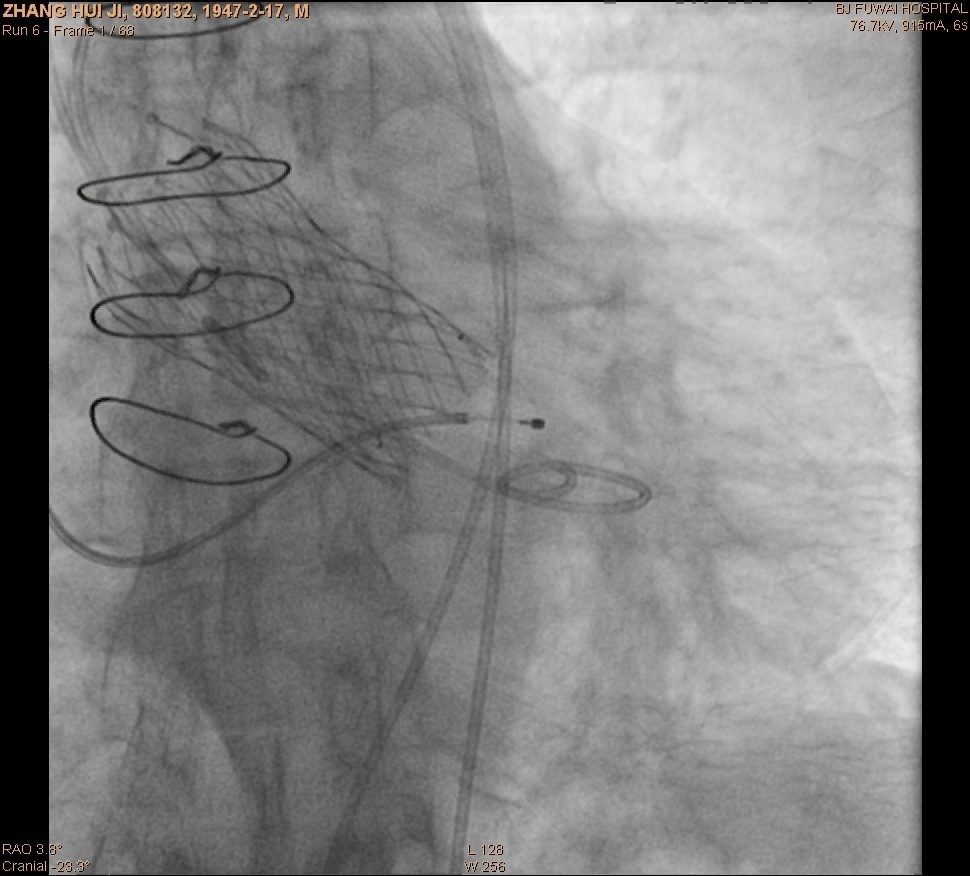

图3:经股动脉途径行TAVR术